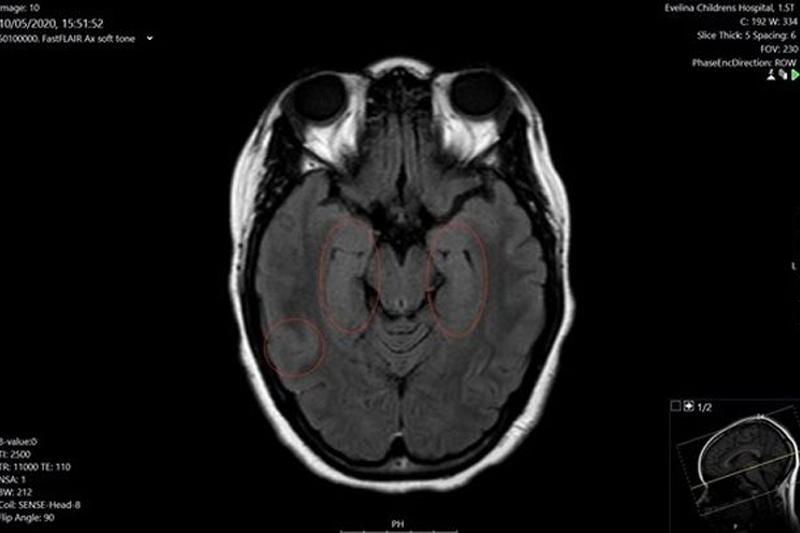

新冠肺炎疫情嚴峻,世界各地都有不少康復者出現後遺症,包括呼吸困難、記憶力轉差,甚至失聲的情況。據外媒報道,來自英國倫敦有一名15歲的少女Nia Haughton感染新冠病毒,一度在深切治療部留醫,待了近兩星期,後來情況轉好康復,卻出現後遺症,包括腦部受損,有幻覺等,性格更似是變了另一個人。